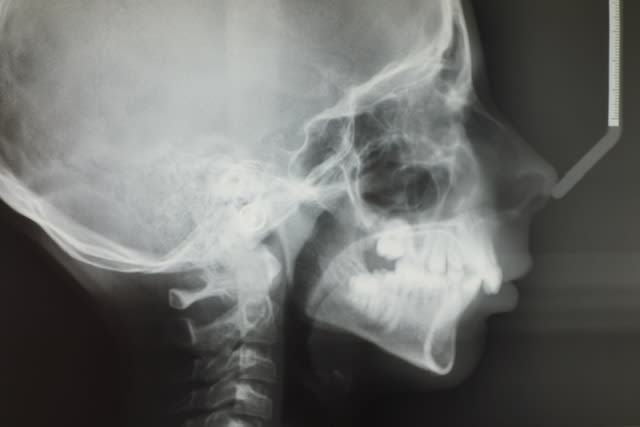

Voici les radios de face et profil.

Analyse de face, j'en ai fait une fois en fac, et c'est tout. Donc, j'en laisse le commentaire à ceux qui en ont l'habitude.

Capucine profil rswyjp - Eugenol